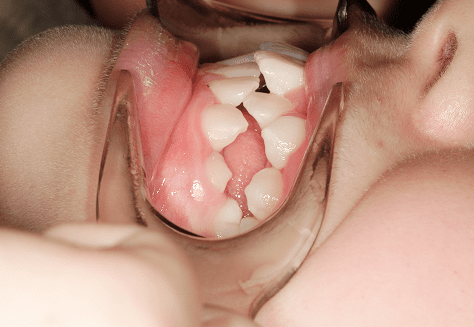

K.Y

治療前

治療後

主訴

歯並びが悪い。永久歯になった時に綺麗な歯並びにしてあげたい。

診断

開口・反対咬合

年齢/性別

10代/女性

抜歯部位

必要に応じて乳歯を抜歯

使用装置

上顎拡拡大床・下顎倍ヘリックス→上下インビザラインファースト→インビザラインフェーズⅡ

保定装置

ビベラリテーナー

基本料金

拡大床:192,000円

インビザラインファースト:358,000円

フェーズⅡ:240,000円 -

診察料金

拡大床時:3,300円

インビザライン時:0円 -

治療期間

8年10カ月